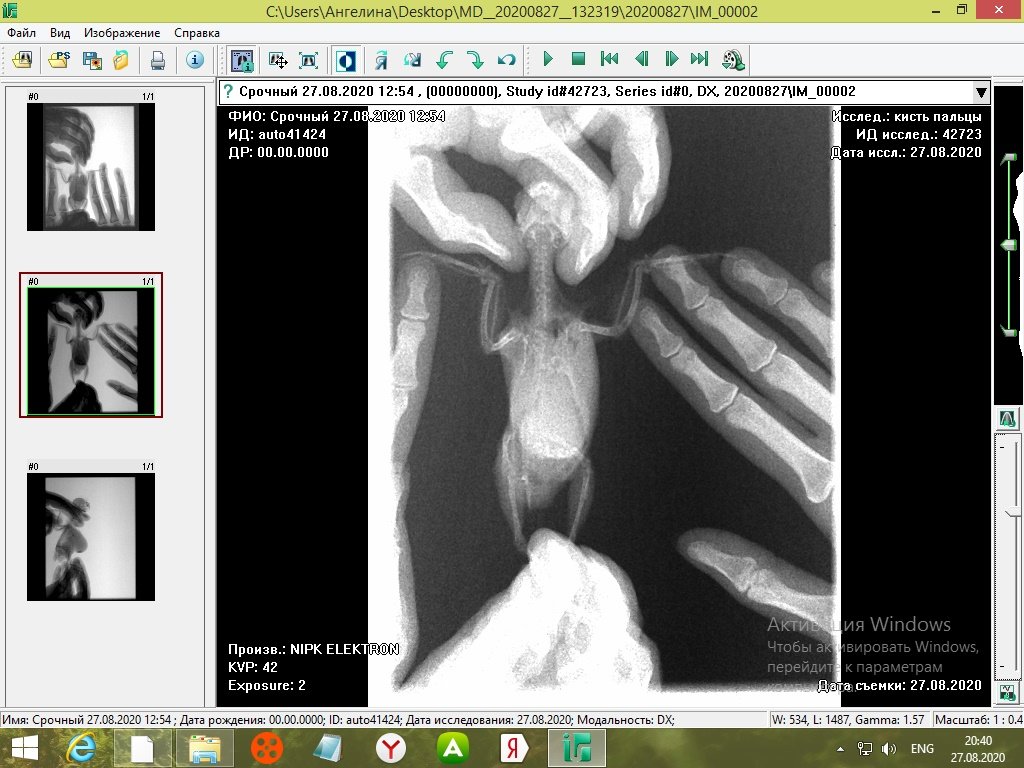

tanushka-sol2020 Опубликовано 27 августа, 2020 Автор #15 Опубликовано 27 августа, 2020 Некадрированные исходные снимки --- щёлкните полосу ниже. Скрытый текст

Кузяныч Опубликовано 28 августа, 2020 #16 Опубликовано 28 августа, 2020 Ох, бедная волнушка... В помёте на шли бактерии (++), слизь (+), жир (+), клетчатку (++)... Есть и непонятные для меня записи... По рентгену на втором снимке справа мне видится что эта огромная припухлость --- растянутый зоб... 18.08.2020 в 17:16, tanushka-sol2020 сказал: Что за опухоль? Она в моих руках меняется: то сморщится, то раздувается как шар надувной... Неужели, действительно зоб?... @tanushka-sol2020, срочно звоните Зосе, просите посмотреть снимки. Мазок из клюва... уф-ф... не знаю пока на сколько он нужен... Если на нистатине птице легче, то давайте его --- придерживайтесь дозировок, что давала вам Зося. Расположите лесенку горизонтально чтоб попугайчик экономил силы. Установите всё как можно ниже к полу. Проверьте, чтоб птичка не пыталась лезть выше и не висла на стенке. Помёт оранжевый... возможно, действительно, печень страдает... Карсил не отменяйте... За гепатовет и как вообще быть я не могу сказать. Нужно чтоб Зося посмотрела рентген. Свяжитесь, пожалуйста, с ней. У меня такое впечатление, что у этой волнушки растянут зоб и от этого плохо уходит и застаивается, протухая, пища.

tanushka-sol2020 Опубликовано 28 августа, 2020 Автор #17 Опубликовано 28 августа, 2020 (изменено) @Кузяныч К сожалению, от нистатина у нее сильно страдает печень. Я не стала ей давать, почти 3 недели принимали. Но срыгивание снова вернулось. Когда я собирала мазок из глотки, она потом срыгнула на одежду. Капли были песочного цвета и консистенция, как каша жиденькая. Но с запахом. Переживаю, вдруг неправильно сделала мазок, впервые же. Во вторнике будет готов анализ. Отпишусь. Рентген делали в больнице, я их кое-как уговорила. Первый "блин с комом", тоже выложила. Вдруг качества нет на снимке, что показал. Завтра Зосе позвоню. Спасибо, что ответили. Эти снимки неудачные выше, племянница скидывала. Я немного контраст отрегулировала, чтобы было видно. Изменено 28 августа, 2020 пользователем tanushka-sol2020